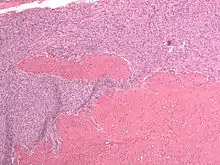

Micrograph of a low-grade endometrial stromal sarcoma. H&E stain.

Low-grade endometrial stromal sarcoma

Low-grade endometrial stromal sarcoma consists of cells resembling normal proliferative phase endometrium, but with infiltration or vascular invasion. These behave less[3] aggressively, sometimes metastasizing, with cancer stage the best predictor of survival. The cells express estrogen/progesterone-receptors.

Microscopy

• Monotonous ovoid cells to spindly cells with minimal cytoplasm.

• Prominent arterioles. Angiolymphatic invasion common.

• Up to 10-15 mitotic figures per 10 HPF in most active areas.

• Tongue-like infiltration between muscle bundles of myometrium.

• May exhibit myxoid, epithelioid and fibrous change.

• May have foam cells or hyalinization in the stroma.